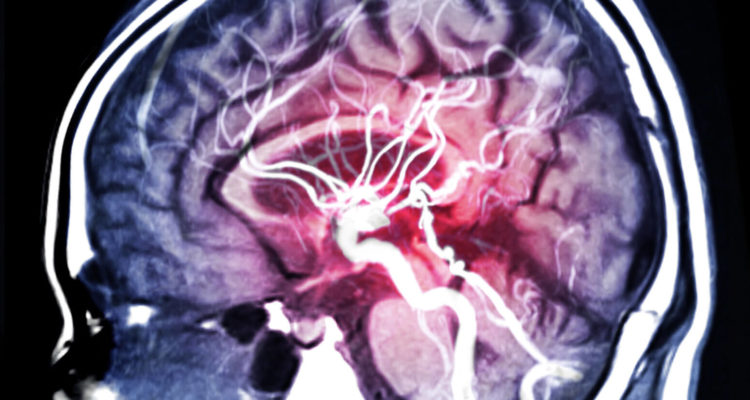

Група вчених, що спеціалізується в Кембриджському університеті на дослідженні інсульту, виявила, що спосіб життя з поганою дієтою, наявністю згубних звичок і нерегульованої ваги, серйозно підвищує ризик інсульту.

Аналізуючи дані з британського біобанку, вони зібрали інформацію про 306 тис. осіб у віці від 40 до 73 років. Протягом чотирьох років відстежувався спосіб життя учасників. Враховувалася дієта, відсутність куріння, індекс маси тіла (<30) і регулярність фізичних навантажень.Далі спостереження тривало близько семи років. За цей час було зареєстровано дві тисячі випадків інсульту. Несприятливим характеризувався спосіб життя з одним із згаданих вище факторів або взагалі без них.

Вчені на чолі з доктором Лоес Ка Раттен-Джейкобс виявили, що такий спосіб життя був пов’язаний з підвищеним ризиком інсульту на 66% в порівнянні зі сприятливим способом життя.З іншого боку, сприятливий спосіб життя визначався як такий, що має всі або три з чотирьох згаданих факторів. Вчені також підкреслюють, що фактори способу життя незалежно асоціювалися з ризиком інсульту.Таким чином, куріння, нездорова дієта, надмірна вага і малорухливий спосіб життя сприяють ризику інсульту.